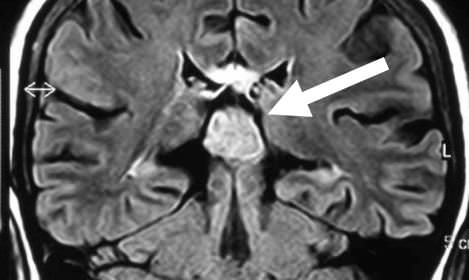

Tumor en la región pineal (pineocitoma)

Índice de contenidos Tumor en la región pineal Historia clínica: Tratamiento: Conclusión: Ver el video en el que se describe caso tumor en la región pineal (pineocitoma): Otros trabajos que pueden interesarle Tumor en la región pineal Historia clínica: Varón de 55 años sin antecedentes de interés. Presenta cuadro progresivo de cefalea que aumenta con … Sigue leyendo Tumor en la región pineal (pineocitoma)